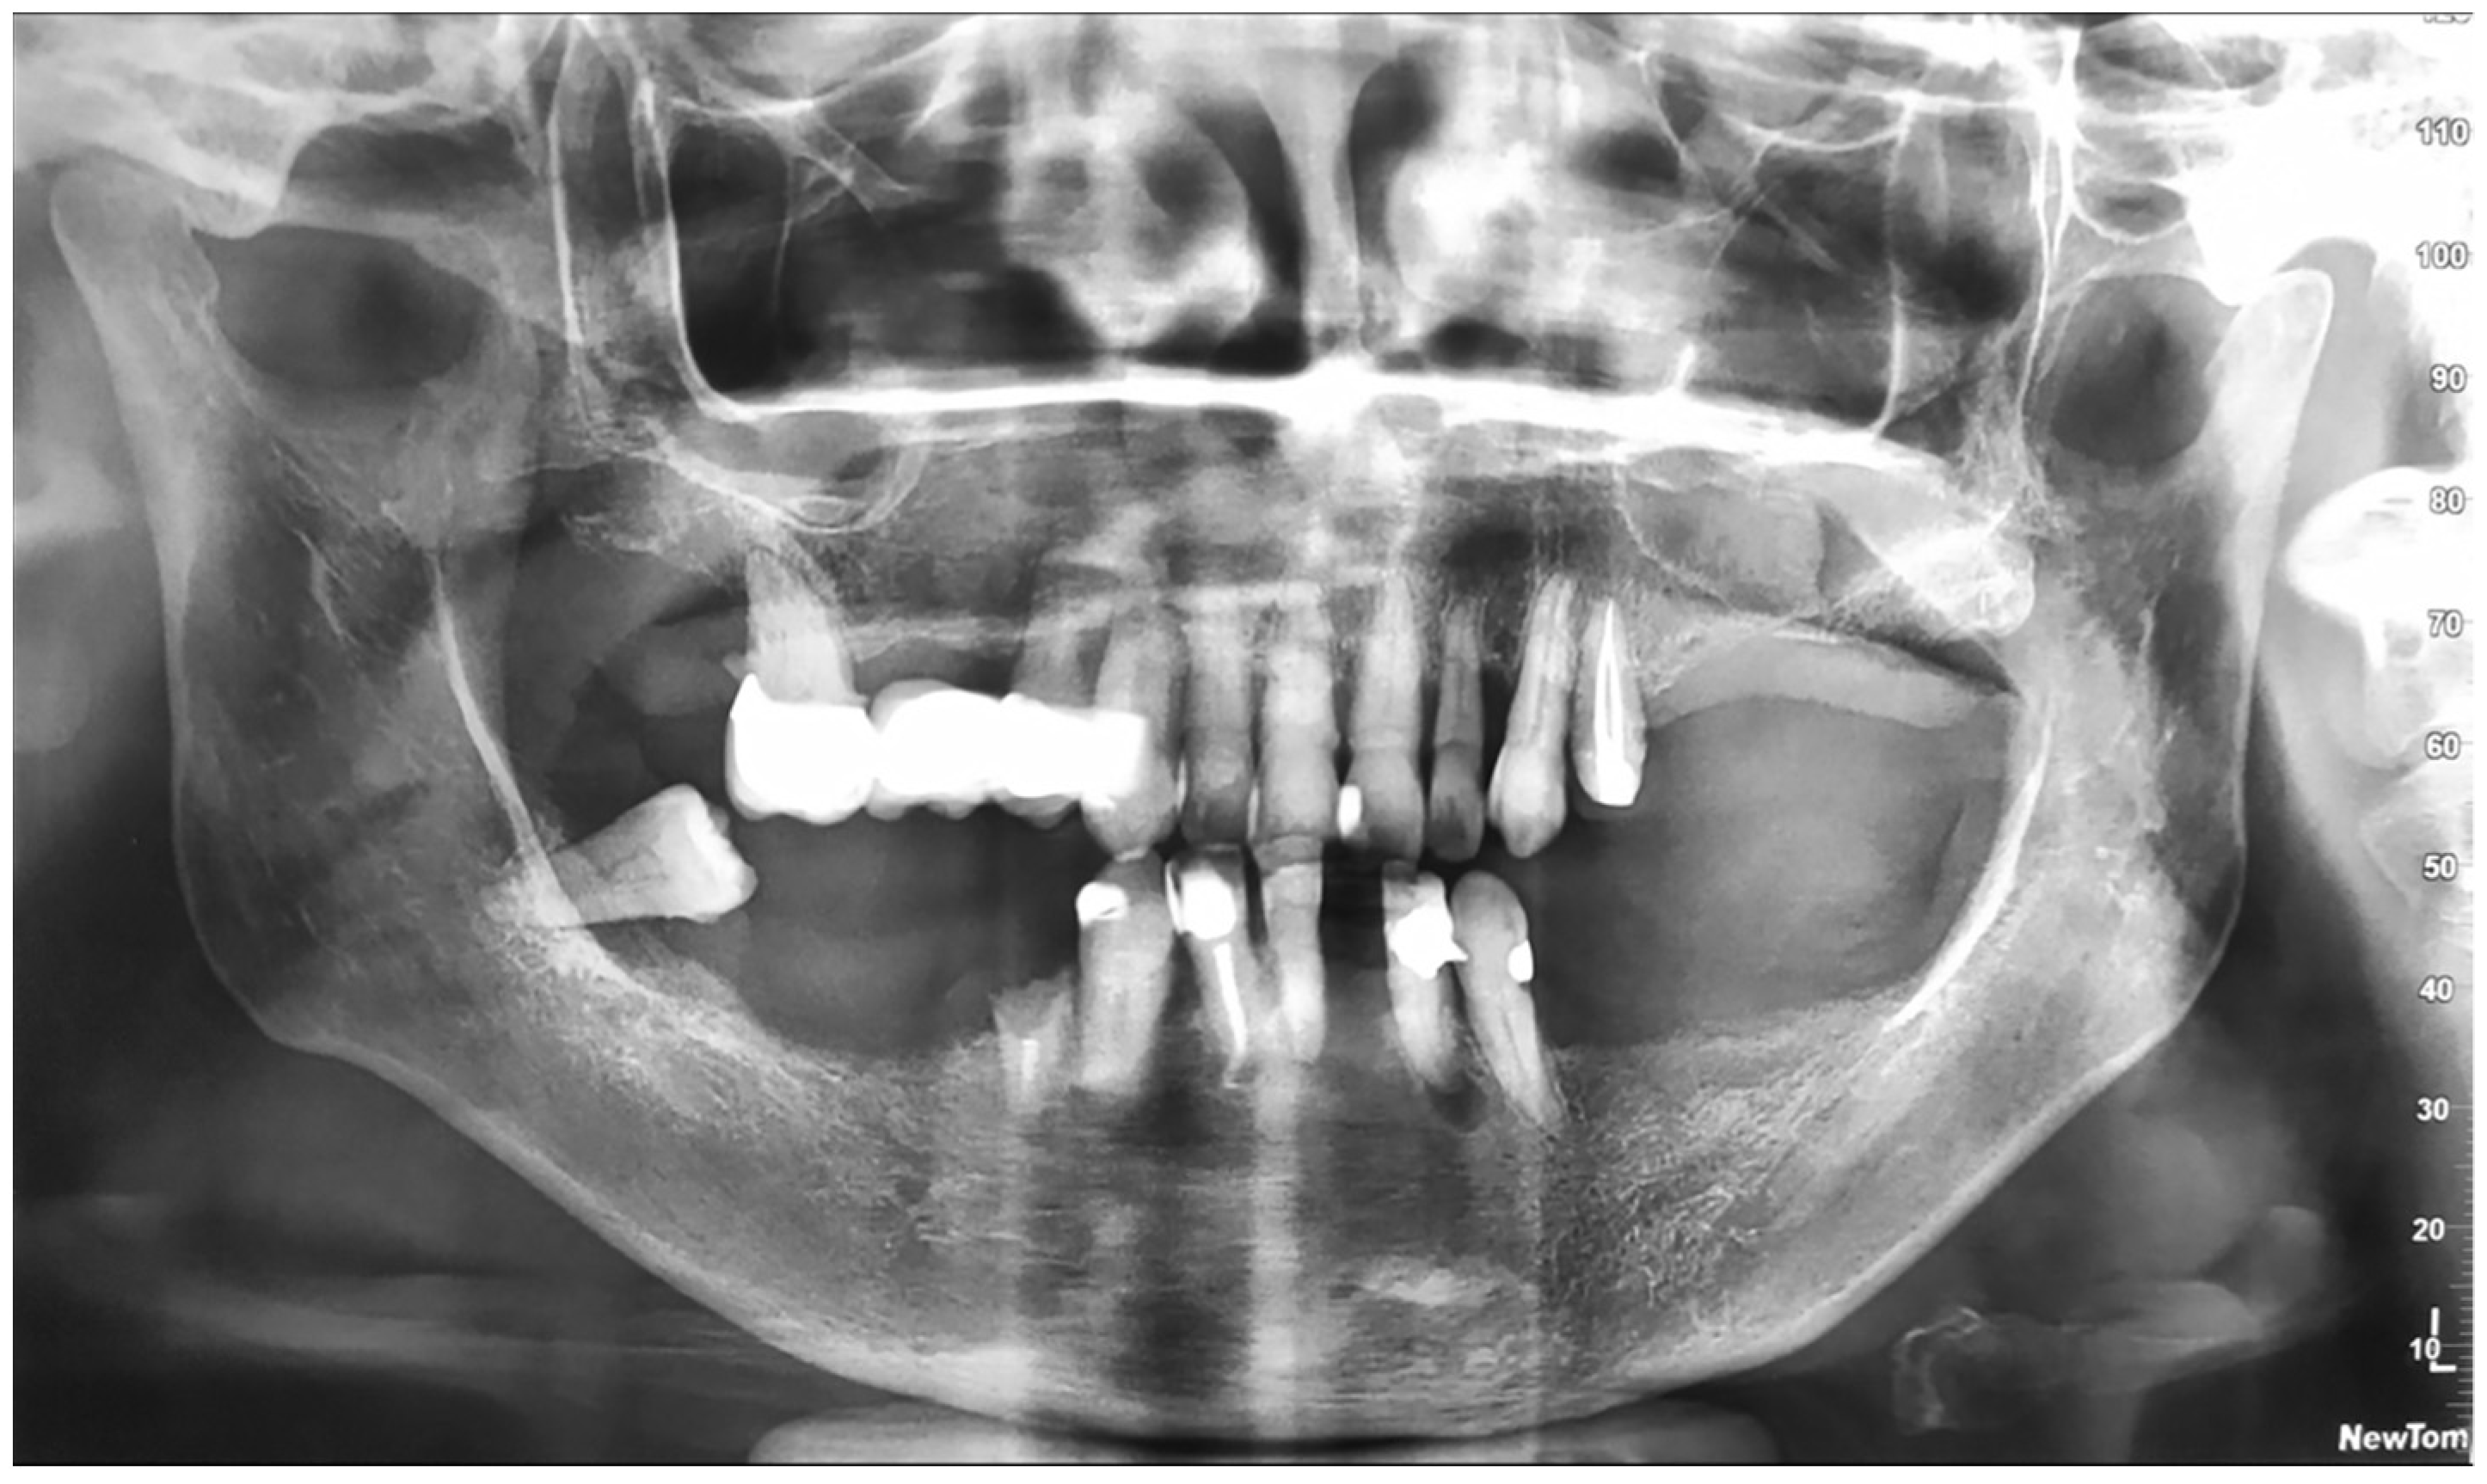

2. Case Report